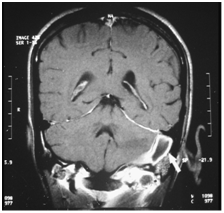

MRI is more sensitive than CT in detecting the thrombus. MRI can show increased signal intensity of the thrombus and detect lateral sinus thrombosis not identified on a routine CT (Figure 12). It shows blood flow, sinus obstruction and subsequent reversal of flow.

Figure 12 MRI showing (arrow) occlusion and dilatation of left lateral sinus.